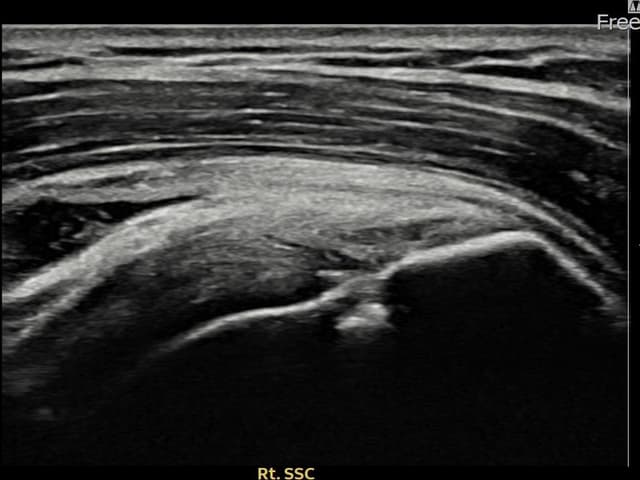

[経過期間: 24.03.04~24.05.10]

[縫縮術] 超音波検査にて右 견갑하근건 関節面側部分断裂(7mm × 3mm (腱厚の約28%欠損))を確認。縫縮術施行後、腱の連続性が回復し、日常生活に復帰されました。